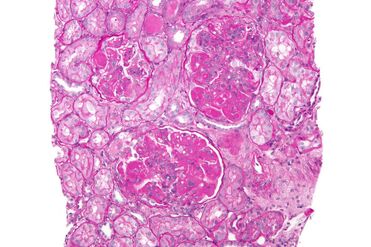

The Role of the Kidney Biopsy in Lupus Nephritis

A kidney biopsy is essential to help rheumatologists figure out the best course of action. After numbing the back under the ribcage, a tiny needle is inserted to grab a small tissue sample, which is then examined under a microscope.

- Normal Kidney: Note the normal kidney in the top right image. The glomerulus (nephron) is one of millions of tiny filters in our kidneys. The white spaces are essential for waste products to fill up and flow into the urine.

- Lupus Nephritis Kidney: Now look at the LN kidney on the bottom, which is affected by the worst form called “class IV diffuse proliferative nephritis.” Notice how there are hardly any large white spaces left. Because this filter is unable to remove waste products, the patient would absolutely go into complete kidney failure without good treatment.